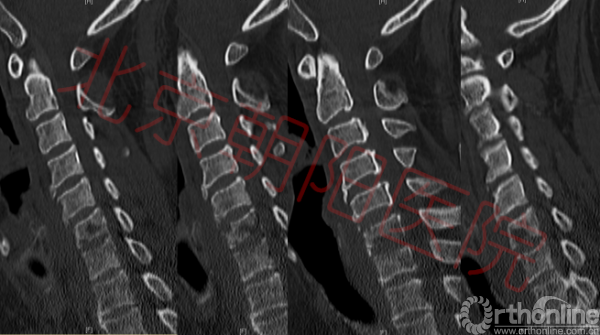

图3:如图可见C6、C7椎体不同程度骨质破坏

颈椎正侧位片显示:颈椎退行性变,C6椎体前缘骨质破坏,欠规整。